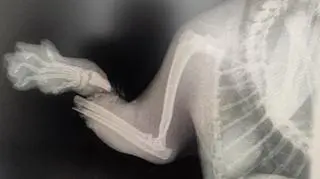

Kotu trzeba było amputować łapę

Wszystko działo się w niedzielę późnym popołudniem, więc dopiero kolejnego dnia właściciel kota udał się do lecznicy dla zwierząt. Tam weterynarz, z uwagi na obrażenia łapy kota, musiał dokonać jej amputacji.